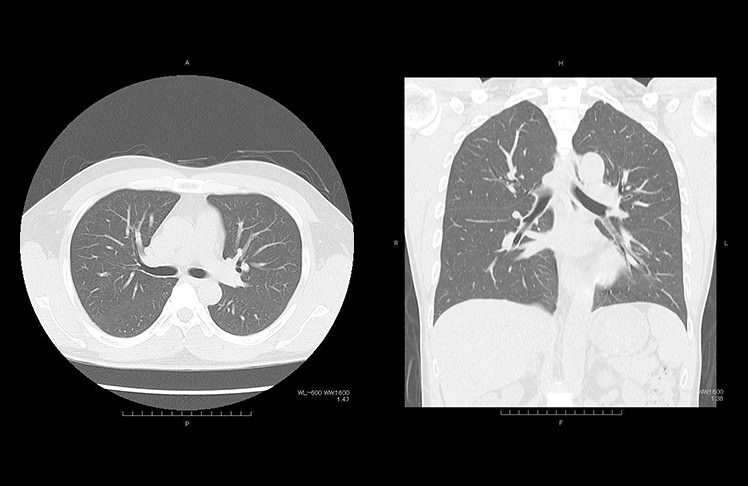

肺ドック

肺ドックでは、胸部単純X線写真(レントゲン検査)と胸部CTを行います。肺内の腫瘍性病変や炎症性病変の有無のほか、気腫性変化や気管支の異常などを調べることができます。肺ドックAでは気腫性変化の画像解析や呼吸機能検査も行います。

喫煙歴の長い方や、受動喫煙が気になる方は一度肺ドックを施行されることをおすすめいたします。